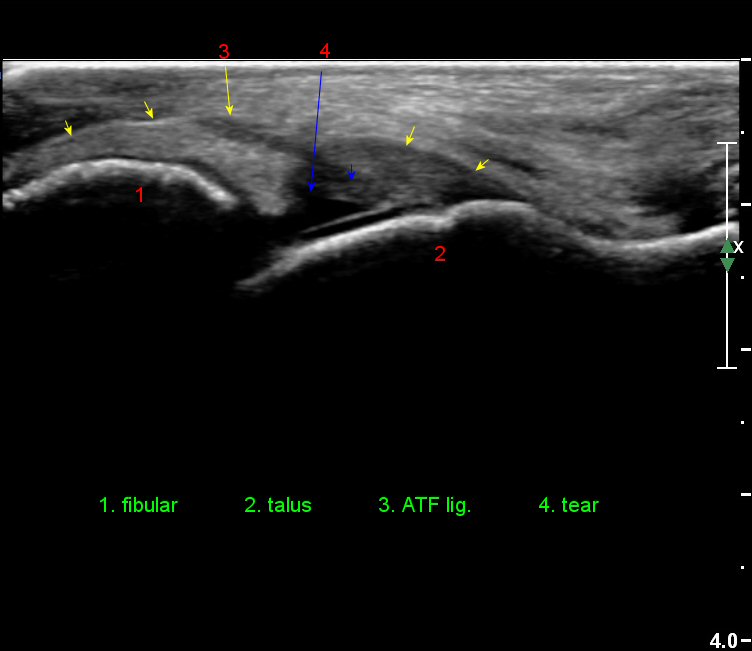

Àü°ÅºñÀδë Á¾´Ü¸é°Ë»ç¿¡¼­ ¾È´ë ºñ°ñ ºÎÂøºÎÀÇ Àú¿¡ÄÚ ºÎÁ¾°ú ºÎºÐÆÄ¿­ÀÌ °üÂûµÈ´Ù(»çÁø 4).

Àü°ÅºñÀδë Á¾´Ü¸é°Ë»ç¿¡¼­ Àü°ÅºñÀδëÀÇ Àú¿¡ÄÚ ºÎÁ¾ÀÌ °¨¼ÒÇϰí ÀδëÀÇ ¿¡ÄÚ°¡

Áõ°¡µÇ¾ú´Ù(»çÁø 3, 4).

Àü°ÅºñÀδë Á¾´Ü¸é°Ë»ç¿¡¼­  Àú¿¡ÄÚ ºÎÁ¾ÀÌ °¨¼ÒÇϰí ÀδëÀÇ ¿¡ÄÚ°¡ Áõ°¡µÇ¾ú´Ù(»çÁø 2, 3, 4).